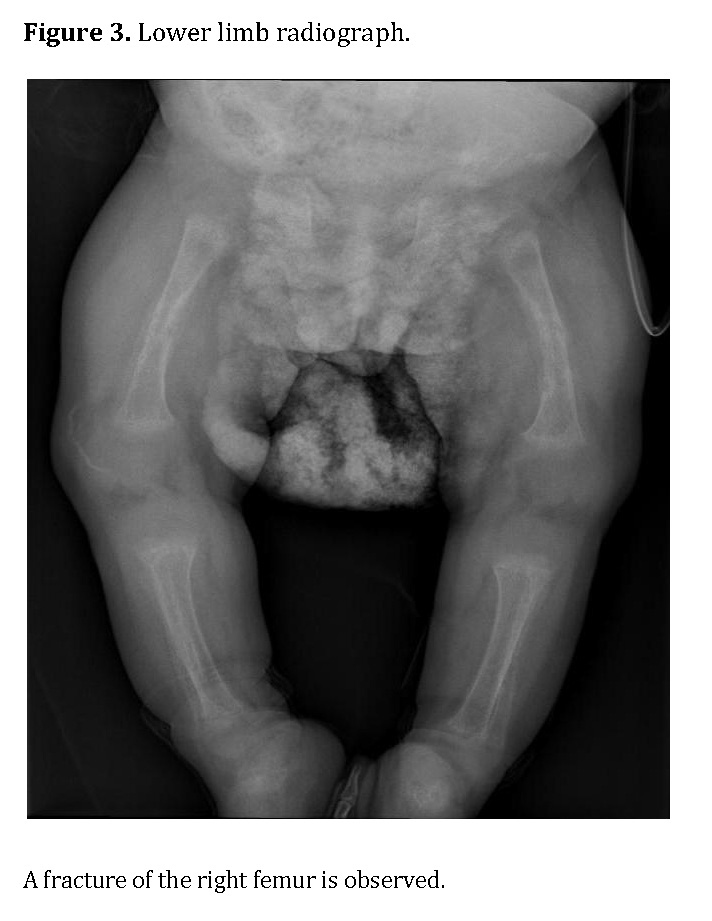

Chest radiography showed bilateral heterogeneous parenchymal infiltrates, pleural thickening, and right-sided rib fractures in the consolidation phase (Figure 1). Radiographs of long bones revealed severe osteopenia, periosteal reaction, and multiple pathological fractures, including the right and left humerus, right ulna, and right femur (Figures 2 and 3).